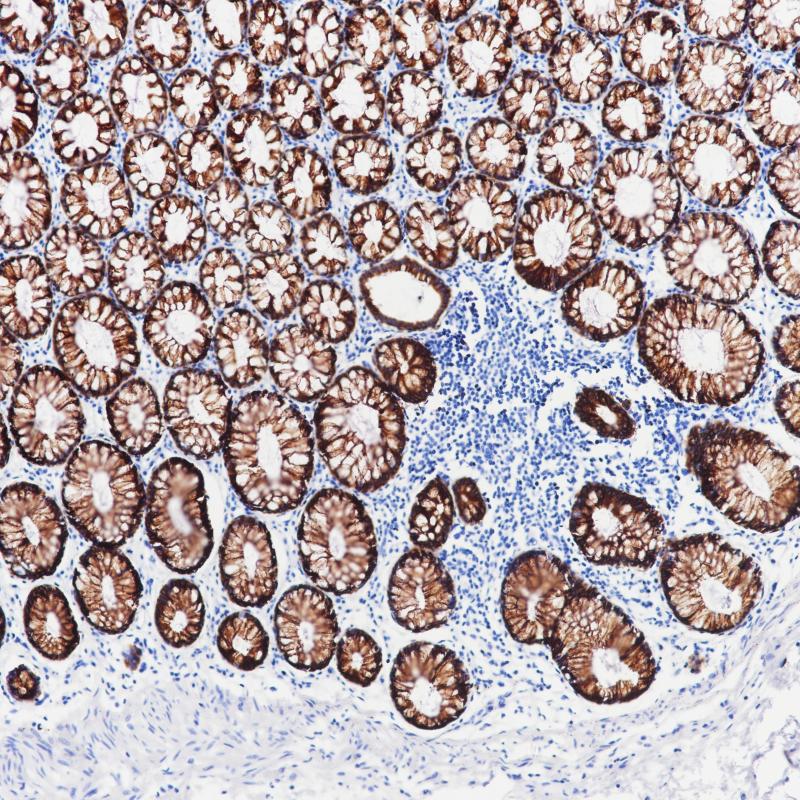

前列腺癌AMACR(BPM6227)染色

AMACR (P504S蛋白)在支链脂肪酸及其衍生物的β -氧化中起作用。AMACR存在于前列腺、肝、胆道、肾、肺等多种组织的线粒体和过氧化物酶体中。在90%以上的前列腺癌中发现了AMACR的弥漫染色模式。AMACR抗体主要用于前列腺癌的临床诊断。